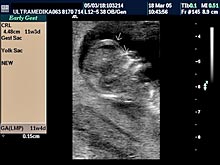

A) Prvi marker za hromozomsku anomaliju (najčešće se misli na trizomiju 21 para hromozoma) je neadekvatna veličina Yolk sac-a (žumančane kese) u 7 nedelji gestacije (GN).

B) Drugi marker je registrovanje postojanje povećane debljine prozračne zone (NT) u vratu ploda-embriona. Obično greške nastaju kada se kontura vrata ploda ne razlikuje od amniona - opne u kojoj se plod nalazi. Osim znanja doktora, rezolucija slike Ultrazvučnog aparata čini ključnu ulogu u merenju ove strukture. Ona-NT se meri u periodu od 9 do 14 GN. Iako je najveća normalna debljina NT 2,5 mm na kraju 14 GN ova vrednost NT može ukazivati na trizomiju ako je registrovana na početku ovog vremenskog perioda. Samo Ultrazvučna kompjuterizovana tomografija može u velikom procentu pouzdano izmeriti ovu strukturu i to na dva načina. Pregled endovaginalnom sondom Braund-band od 8-4MHz, često zbog pozicije ploda nije u stanje da adekvatno registruje NT. Pregled se može znatno zbog toga produžiti i ne mora tačno izmeriti debljinu NT. Međutim u ovakvim situacijama upotrebom Braund-band sondi koje koriste ceo opseg ultrazvučnih talasa od 12 do 5 MHz, pregled se u velikom broju slučajeva završava pregledom preko prednjeg trbušnog zida. Ovaj transabdominalni pregled ima prednosti zbog mogućnosti boljeg pozicioniranja ultrazvučne sonde

u odnosu na položaj ploda, pri čemu je kvalitet slike neuporedivo bolji u odnosu na pregled vaginalnom sondom. Jedino konstitucija trudnice donekle ograničava pregled preko prednjeg trbušnog zida (mokraćna bešika ne mora biti puna).